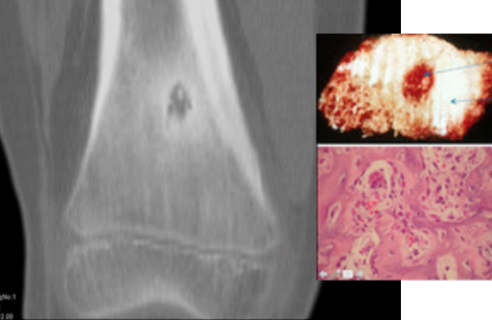

Osteoid osteoma central nidus, woven bone

Osteoid osteoma woven bone